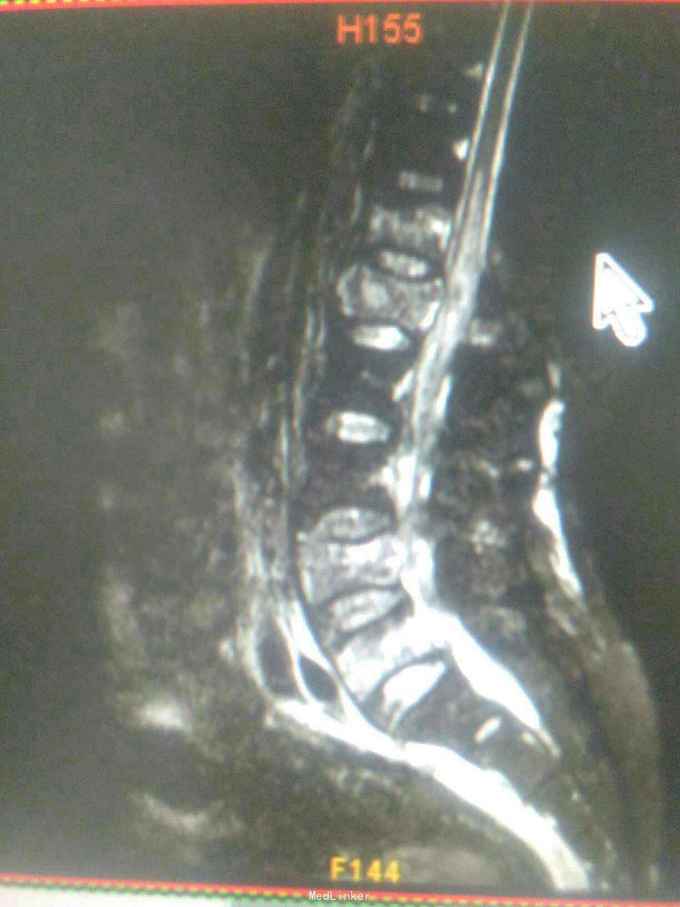

患者因高处坠落致腰痛部疼痛,双下会活动受限9小时入院。患者9小时前从3米高处坠落,腰骶部先着地,即时觉双下肢麻木,不能活动。

查体腰背部压痛,双下肢肌力0级,肌张力减低,会阴区,双下肢痛觉减低,触觉,精细觉正常,腱反射未引出,肛门反射消失,括约肌松弛。

诊断腰1,腰4椎体爆裂性骨折,腰5椎体压缩性骨折,脊髓圆锥损伤双下肢截瘫。患者入院后48小时内行了腰椎后路腰1.4椎体切开复位椎弓根钉内固定,腰1椎板切除,椎管扩大成形,横突间植骨融合术。